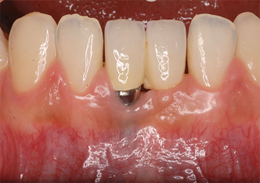

Pérdida de un diente único

La pérdida de un diente único es cuando un solo diente se ha caído o ha sido extraído, y se necesita un implante para reemplazarlo.

Los pacientes pueden notar un espacio donde solía estar el diente. Esta condición puede afectar la estética y la función masticatoria.

El tratamiento incluye la colocación de un implante dental para restaurar el diente perdido.